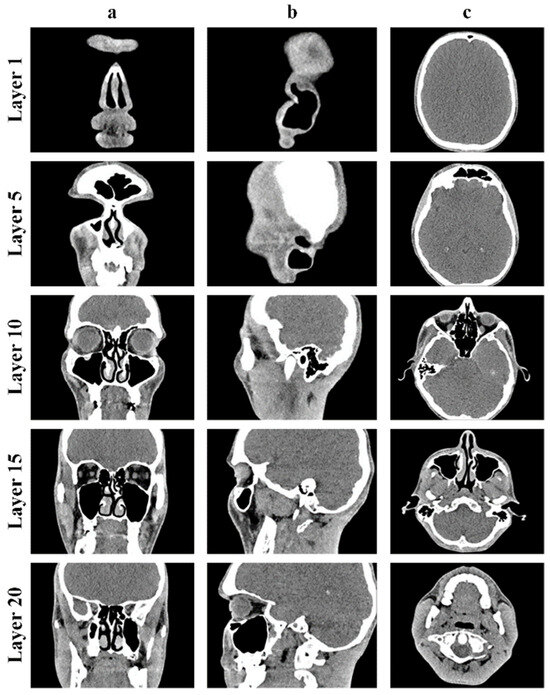

The obtained CT results for the upper respiratory tract, particularly the human nasal cavity, are depicted in Figure 1 across three distinct projections: frontal, sagittal, and axial planes.

The CT images above clearly show the boundaries between the airways (dark area of the CT images) and soft or bone tissue (light area of the CT images).

Figure 1. CT results of the human nasal cavity: frontal plane (a); sagittal plane (b); axial plane (c).